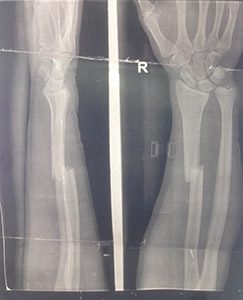

Изображения повреждения костей